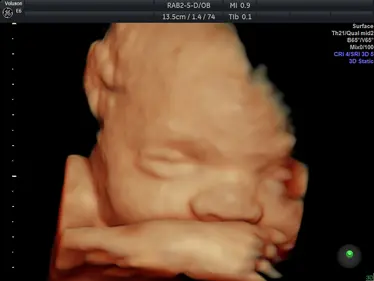

Gallery: 4D Scan Images & Videos

All of the baby scans we perform here at First Encounters are carried out using top-quality ultrasound equipment. For 3D/4D scans, we use the GE Voluson E6, featuring genuine HDLive technology. GE Healthcare are the world’s leading providers of pregnancy scanning equipment, and HD Live scans give an unparalleled level of detail and clarity.

Scroll down to view some examples of the 4D scan images and videos our sonographers are able to capture.

4D Scan Images

During your 3D/4D scan, we’ll capture multiple photographs of your unborn baby, giving you and your family a set of stunning keepsakes that you’ll treasure forever. All of your scan images will be available to download from photocloud™, plus we can provide glossy souvenir photos for you to take home.